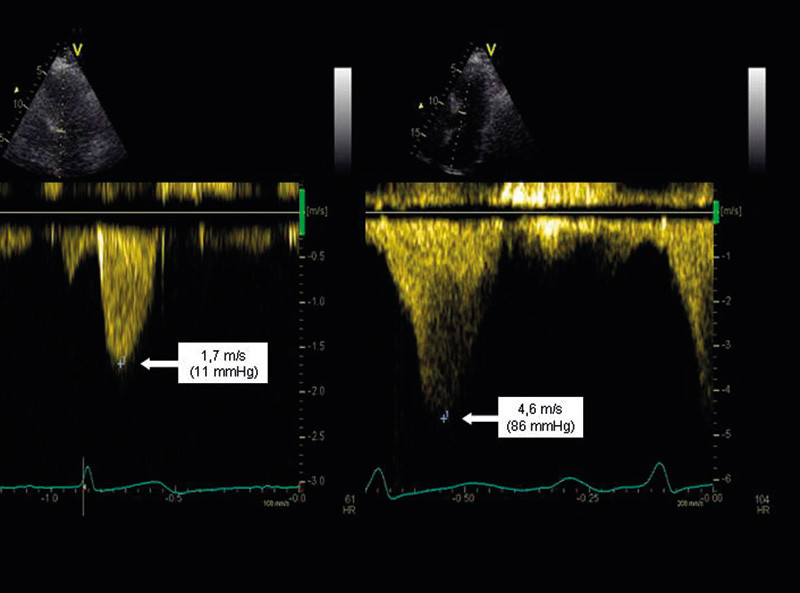

Det er vist at over en tredel av alle pasienter med hypertrofisk kardiomyopati uten utløpsobstruksjon i hvile kan ha signifikant obstruksjon ved belastning (1). Obstruksjonen øker trykkfallet i venstre utløpstractus, og man anser at et maksimalt trykkfall i hvile på > 30 mm Hg og/eller et arbeidsindusert trykkfall på > 50 mm Hg er av klinisk betydning. Disse verdiene blir brukt som grense for behandling med alkoholablasjon eller myektomi (2).

Trykkfallet beregnes fra blodstrømshastigheter registrert med kontinuerlig doppler fra hjertets apeks ved hjelp av den forenklede Bernoulli-likningen ΔP = 4v² (der ΔP er trykkfallet målt i mm Hg og v er maksimal blodstrømshastighet målt i m/s) (3).

Obstruksjonen i utløpstractus kan føre til at fremre mitralseil trekkes fremover i systole og forårsake såkalt SAM-fenomen (systolic anterior movement). Dette kan igjen gjøre det trangere i utløpstractus, med ytterligere økning av trykkfallet, og det kan også oppstå en betydelig mitralinsuffisiens. Blodstrømmen fra denne mitralinsuffisiensen kan være lokalisert nær blodstrømmen i utløpstractus, slik at det kan være vanskelig å skille disse. Ofte får man deler fra begge hastighetssignaler i samme registrering. De kan imidlertid differensieres ved at blodstrømmen i mitralinsuffisiensen begynner tidligere enn blodstrømmen gjennom utløpstractus og ved at obstruksjonen gir en sensystolisk, kraftig akselerasjon av blodstrømshastighetene, med et karakteristisk knivbladformet signal (fig 2).